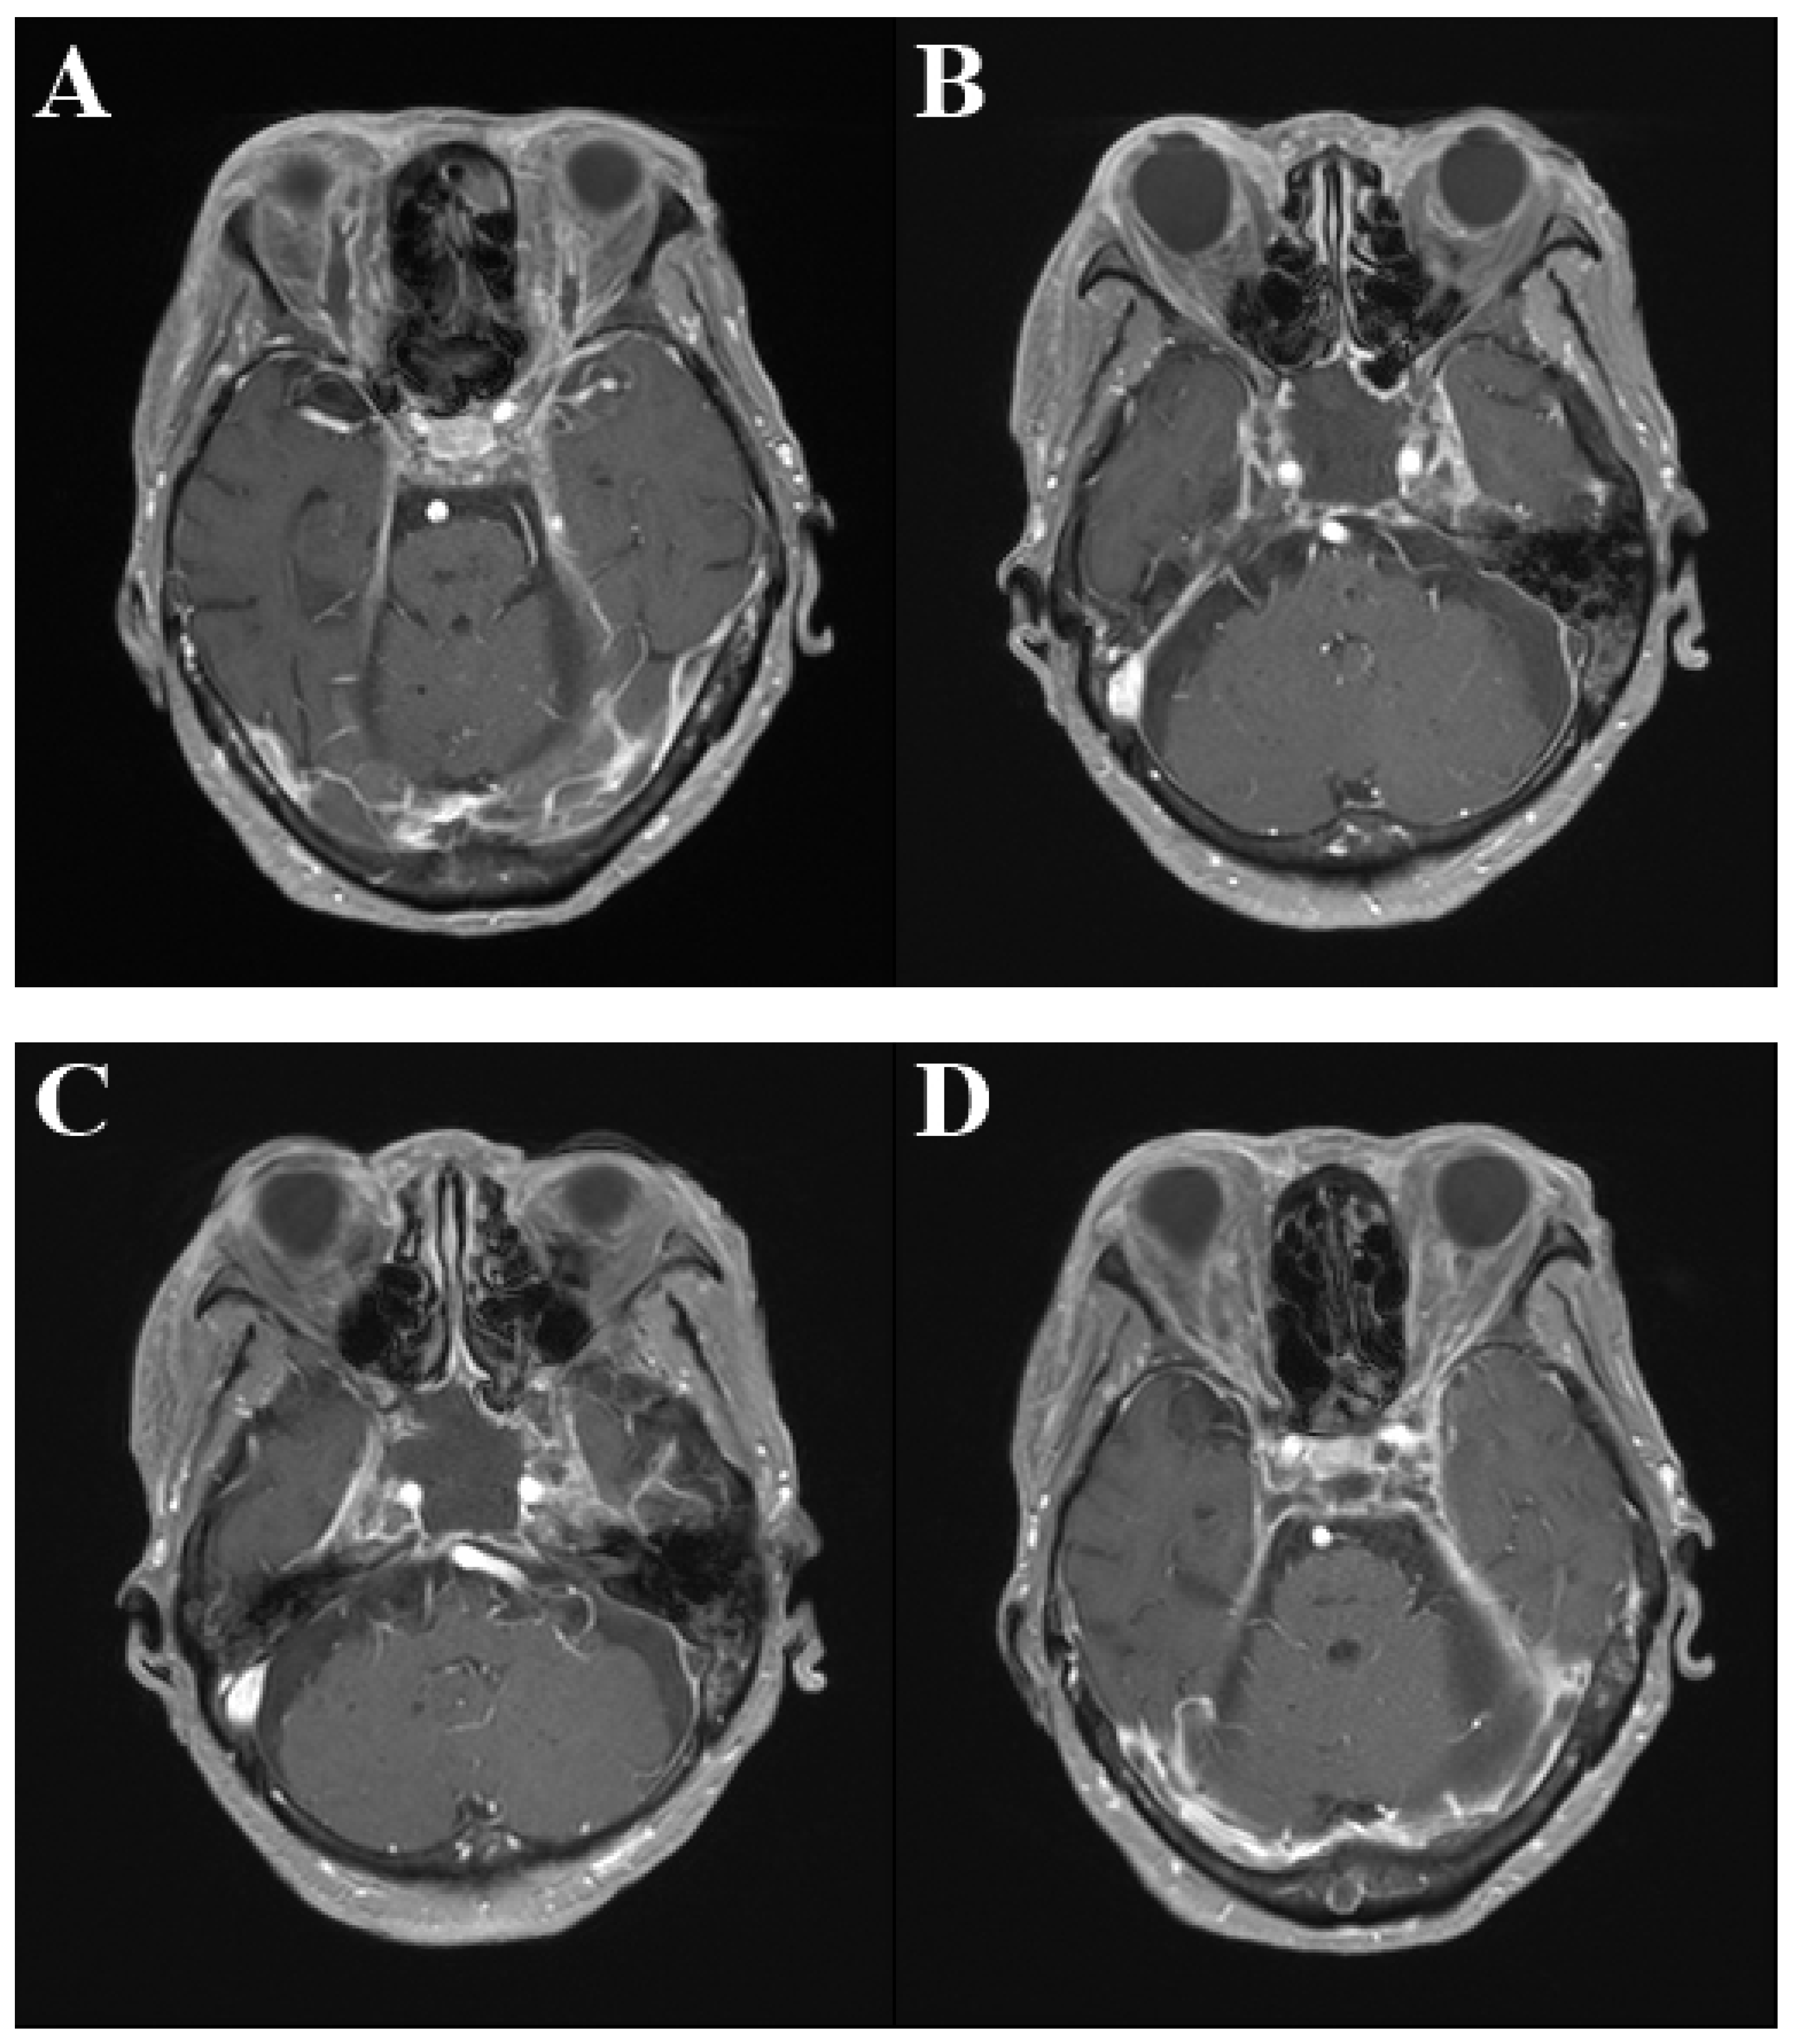

2. Case Presentation